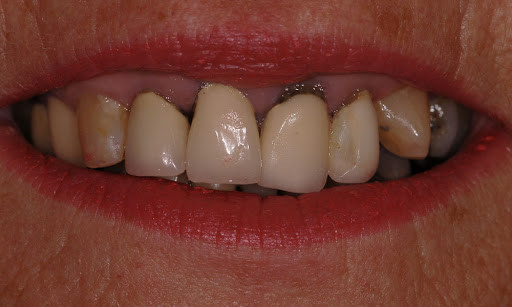

Black Teeth: Symptoms, Causes and Treatment

Black teeth can be a concern for many people; a black tooth will affect your smile and impact on your confidence. If you have a black tooth, read on to find out more about the symptoms and causes and treatments that may be available.

What causes a tooth to go black?

There are many reasons why a tooth can begin to go black, anything from simple staining to the death of the tooth can cause blackness and darkening.

Poor oral hygiene

Poor oral hygiene can cause your tooth to go black. In the early stages this is likely to be staining from substances like tobacco, red wine and strongly colored food. If your oral hygiene routine is not thorough enough to remove the acid-excreting bacteria each day, the acid will slowly eat away at your tooth.

As the tooth gets eaten away, tooth decay sets in. Tooth decay naturally looks black and can give the appearance of a black tooth. This gives the look of rotten teeth and is a classic result of not looking after your teeth for a considerable period of time.

The death of a tooth

When a tooth dies, the blood supply – which gives the tooth its natural, healthy color – will stop. Because the tooth is not receiving the nutrients it needs, it will begin to necrotise, darken, die and slowly go black.

Will my tooth go black after root canal?

A common misconception is that a tooth will go black after a root canal treatment. Teeth will often go black before root canal treatment as the tooth rots and decomposes on the inside. If root canal treatment is done well, all of the decomposing tissue will be removed and the blackness will not get worse. There may, however, be some mild darkening of the tooth after a root canal, depending on exactly how the root canal treatment is done and with which material.

Treatments for a black tooth

Black spots on teeth can be treated quite simply, these can often be caused by a small pit or chip in the tooth which either picks up staining or has a small amount of decay. Your dentist can usually remove a small amount of tooth around this area, removing the staining and/or decay and placing a some tooth-colored bonding material over this area. The tooth bonding will blend in naturally with your surrounding teeth, making the repair invisible.

Dead tooth whitening is also possible. This is whitening with a peroxide gel which can whiten teeth significantly; however, sometimes teeth whitening alone is not enough to whiten a dead tooth and some form of restorative option needs to be considered, either a dental veneer or a dental crown.